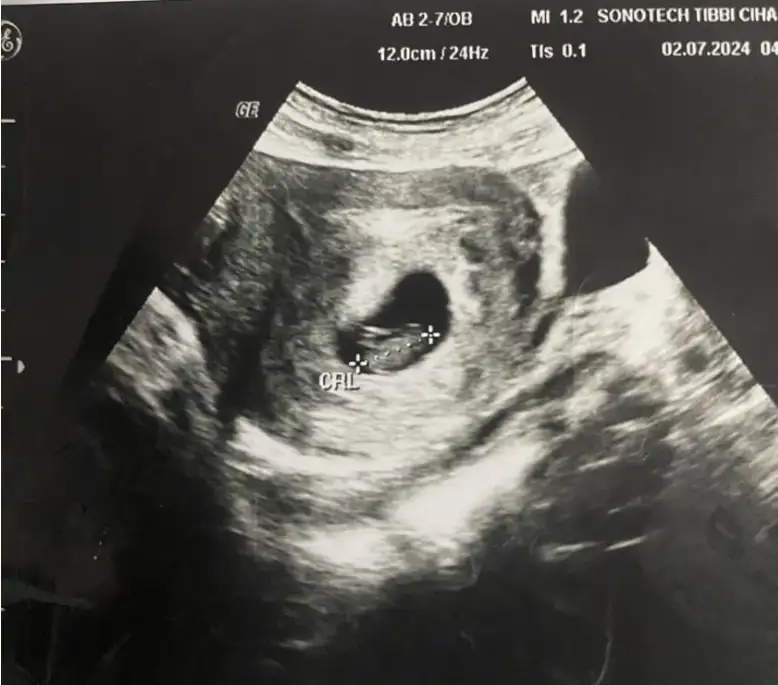

Bana yasini ve hamile kaldin ayi yaz tahmin edeyimMerhaba bize de tahmin de bulunabilir misiniz 10 haftalık

Bana yasini ve hamile kaldin ayi yaz tahmin edeyim

Merhaba nub göremedm Sanki ben ama ortada bsy var gb hafıf dik o mu acabaResim yüklemeyi unutmuşum![]()